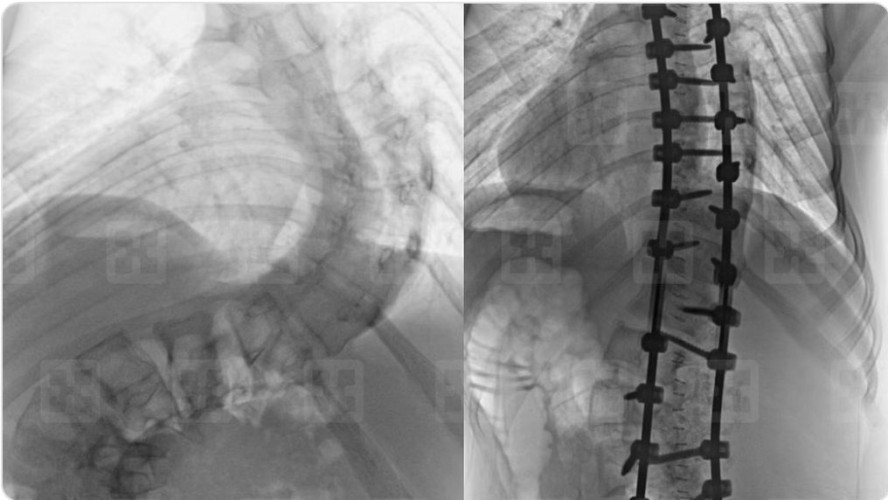

وأضاف د.خليفة أن أكثر الحالات تعقيدًا، حالةٌ تعود إلى سيدة عمرها 38 سنة، وبلغت نسبة الانحراف عندها 90 درجة، وتكللت عمليتها -ولله الحمد- بنجاح كبير، وأكد أن المريضة بدأت في الوقوف والتحرك في اليوم الأول للعملية، كما أنها استعادت المظهر القويم، بعد تعديل وضعية الحوض والكتف، إضافة إلى أن طولها مع النجاح الكبير للتعديل زاد بنحو 6 سم، وخرجت من المستشفى وهي بصحة جيدة بعد أن أمضت 6 أيام قيد التنويم والعناية الصحية الحثيثة.

واستطرد د.خليفة أن باقي المرضى وهم فتاتان وفتى واحد، كانت درجات انحراف العمود الفقري لديهم أقل حدة، وخضعوا لعمليات تعديل ناجحة، وجميعهم -بمن فيهم الحالة الأولى- استطاعوا التحرك على أرجلهم في ذات يوم العملية، وتخلصوا من كل الأعراض التي قادتهم إلى المستشفى بعد فترة قصيرة من إجراء العملية، وعادوا إلى الحياة الطبيعية.